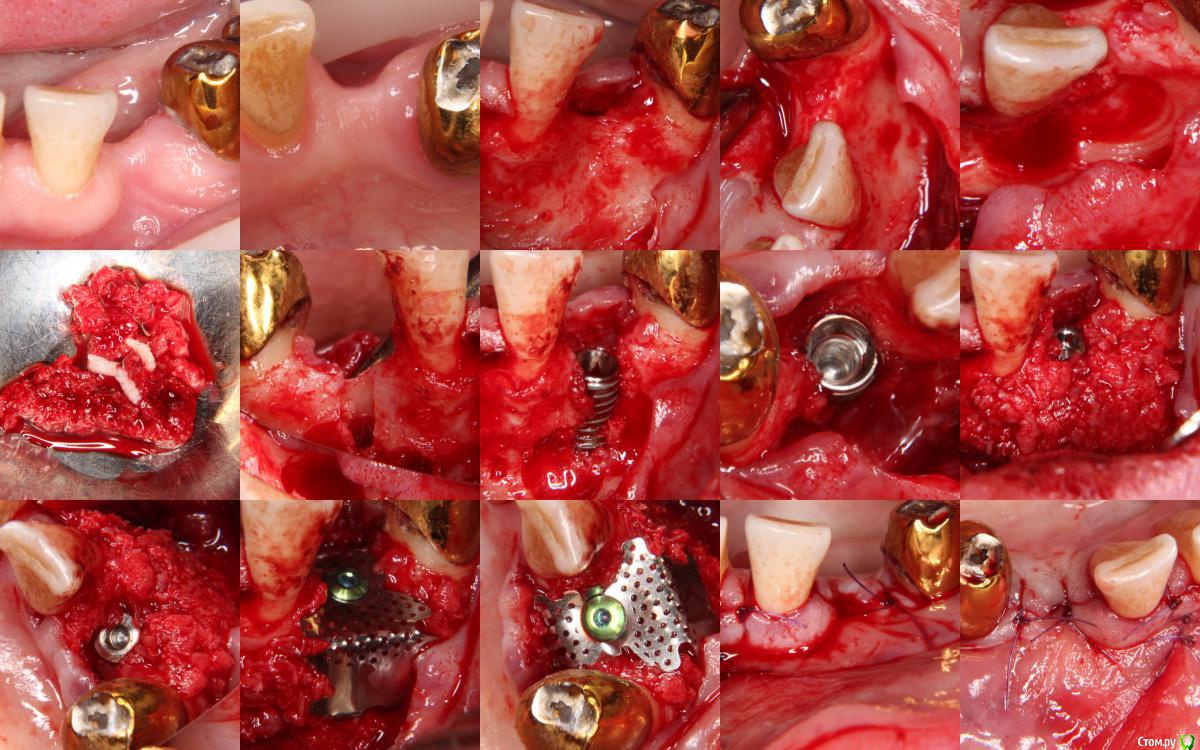

Astafev Опубликовано 6 января, 2015 Автор Поделиться Опубликовано 6 января, 2015 Новый спейсер лучше старого Мембрана новая с дырками в ногах?Сетка для трехстеночных дефектов (С-Type 3 Wall), мне кажется они самые удобные(можно почти под любой дефект обрезать)На счет спейсера-это да, гораздо удобнее 1 Ссылка на комментарий

Astafev Опубликовано 6 января, 2015 Автор Поделиться Опубликовано 6 января, 2015 Спасибо за клинический случай.Лично у меня негативное отношение к чистой ауто - пару раз все лизировалось напрочь, что очень неприятно при уже установленном имплантате. Упаковано довольно плотно, в практике есть подобные случаи-результат нравится.Конкретно эта работа из разряда "бюджетных"и малоинвазивных, поэтому выбор пал на такую методику 3 Ссылка на комментарий

Astafev Опубликовано 6 января, 2015 Автор Поделиться Опубликовано 6 января, 2015 Из разряда "бюджетных" Лиопласт вроде не дорогойЛиопласт как альтернатива ауто, во избежании донорского участка при заборе своей кости, в этом случае забор ауто и постановка имплантата-одна область(причем с помощью АСМ это происходит очень быстро и в большом объеме) 1 Ссылка на комментарий